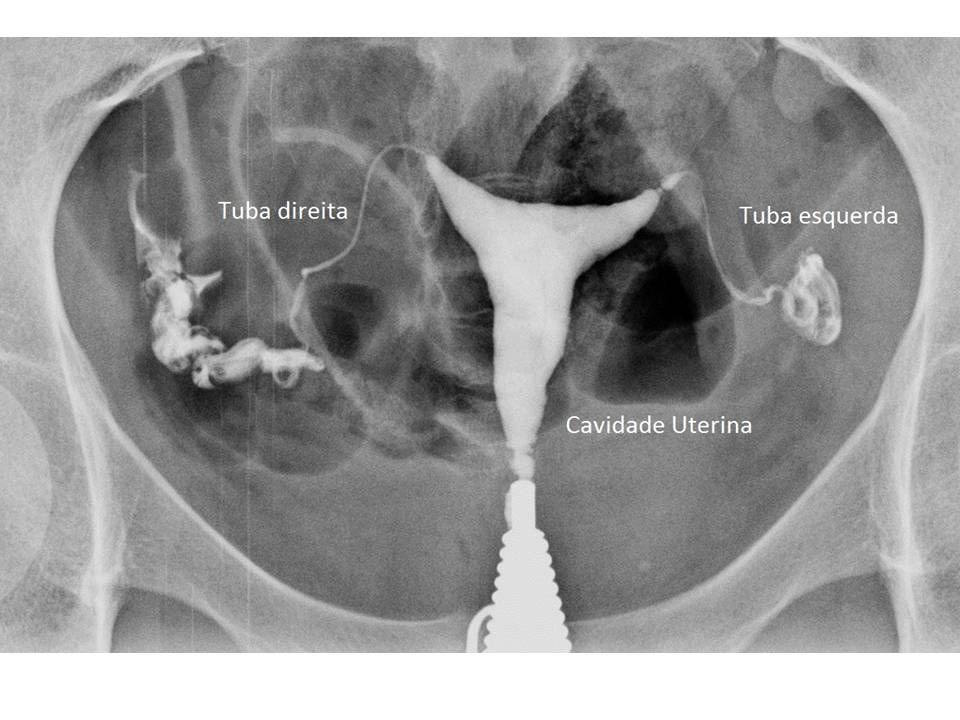

Fator Tubário

A patência das tubas é essencial para que o espermatozóide encontre o óvulo.

- Exame Padrão-Ouro:Histerossalpingografia (HSG).

- Timing: Deve ser realizada na fase folicular (após a menstruação e antes da ovulação) para evitar irradiar uma possível gestação inicial.

- Achado Crítico: A presença de Hidrossalpinge (tuba dilatada com líquido tóxico) reduz a taxa de implantação na FIV pela metade. A conduta recomendada é a salpingectomia (retirada da tuba) antes da transferência embrionária.